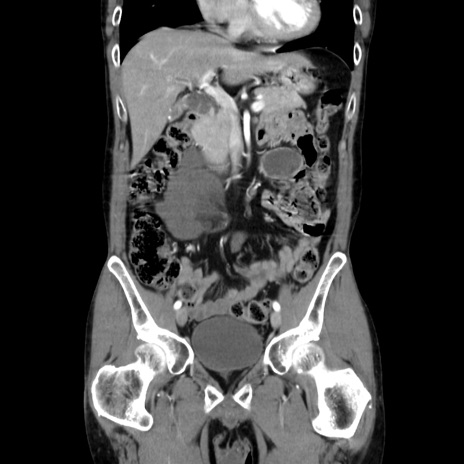

症例37(冠状断像)

【症例】40歳代 男性

【主訴】腹痛

【現病歴】4時間ほど前に電車に乗車中に臍部上より腹痛出現。徐々に増悪し起立困難となり、救急外来受診。生ものは数日食べていない。今朝お雑煮を食べた。

【身体所見】BT 36.8℃、BP 117/84mmHg、HR 91/min、SpO2 97%、苦悶様、腹部:臍上部広範囲圧痛あり、反跳痛±

【データ】WBC 8100、CRP 0.03